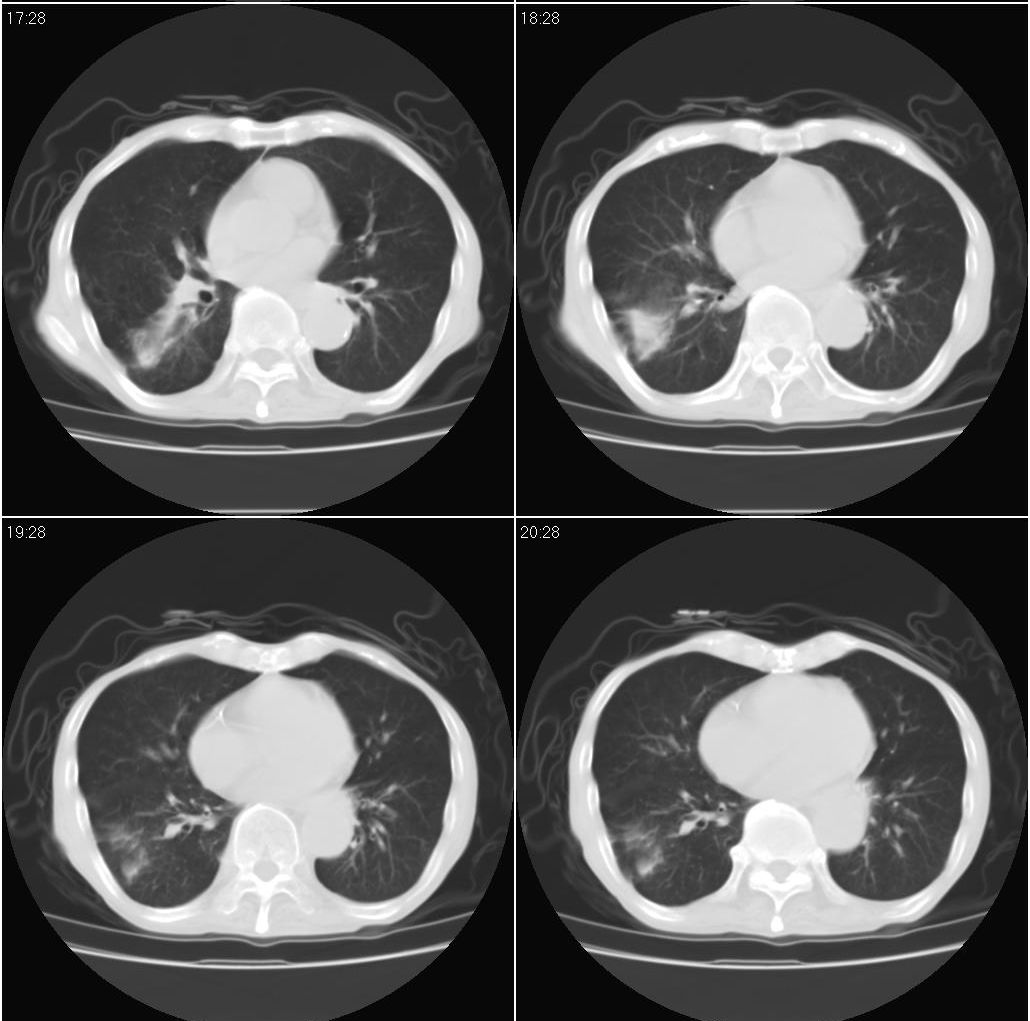

标题: 病例追踪

该患者通过抗炎治疗明显好转:当时患者消瘦,实是因为患者进食量不多。患者有食道癌,因发生原发肺癌的机率并不高,当时的ct片除了增强感觉有强化外(其实这信息也并不确定,因为是外院ct),其实并没有发现支气管腔改变等直接征象。经过治疗,患者现在一般情况良好。以下是9月22日的复查片,发现病灶吸收明显。纵隔窗就不上传了。

[本贴已被 fanshl 于 2008-9-26 10:52:11 修改过]